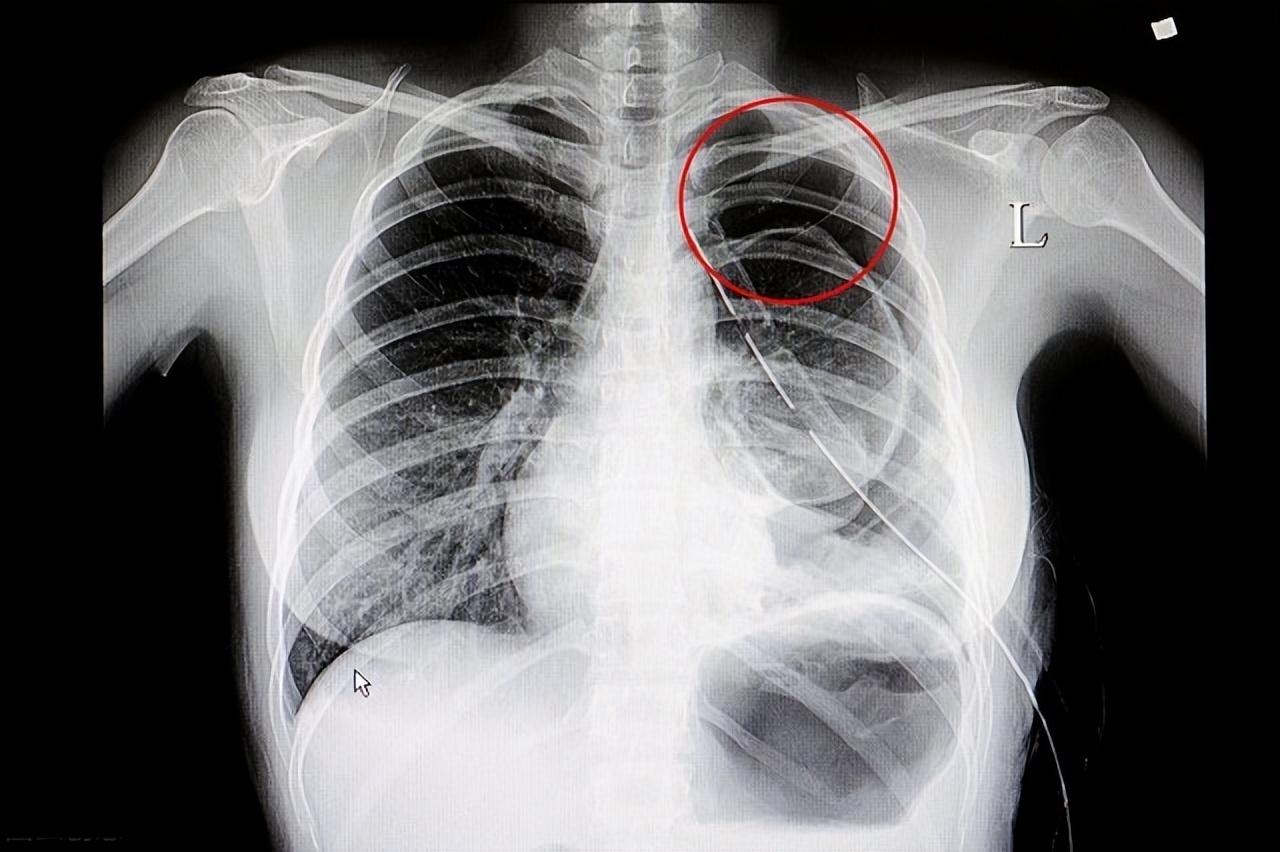

一旦怀疑气胸,应及时就医。 医生通常根据病史、典型症状和胸部听诊来初步判断,然后通过普通胸片或胸部CT来确诊。对于肺压缩面积小于20%、首次发作且病情稳定的气胸,可采取保守治疗,如高浓度吸氧和使用镇静剂、止咳剂。大多数患者可在7-14天内自行吸收。